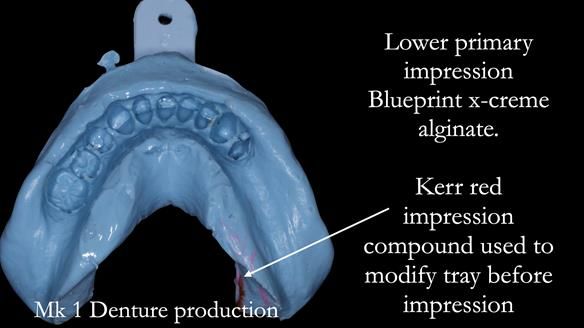

This newsletter describes the full protocol workflow of a complete upper denture and a lower partial denture for Jo.

The clinical situation and treatment process is shown in detail below. I provided the clinical work. Rowan Garstang provided the technical work. This treatment took 25 visits over a period of 12 months.